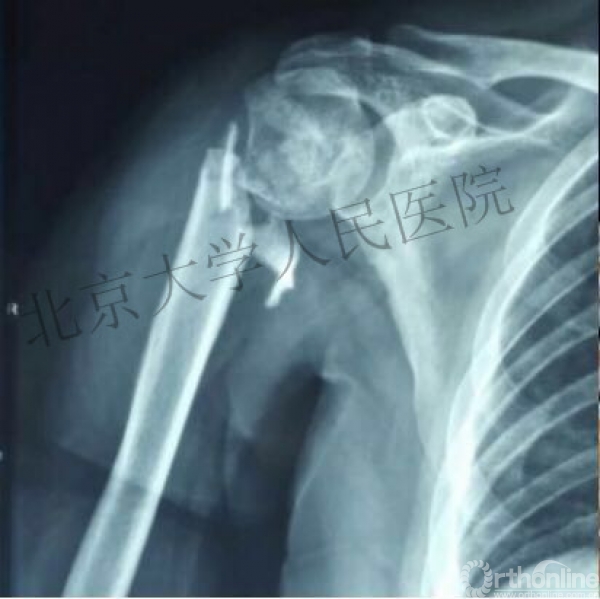

另一个留有遗憾的病例,您的选择?PHN?

临床中的广泛内固定治疗不断地提出思考